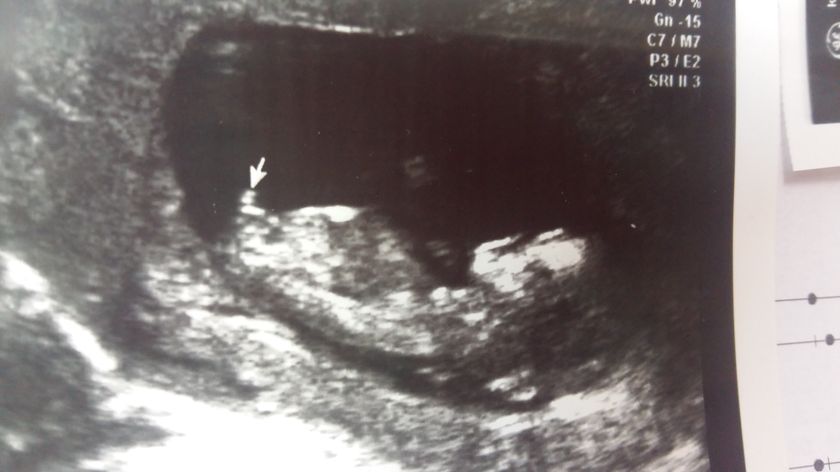

Дождалась я таки 1й скрининг. Ребенок мой категорически отказывался показывать все, что нужно. Стоял на голове, прижимал подбородок к груди, закрывался руками. Короче час меня мурыжили. Приходилось ходить гулять. В общем все хорошо. Не идеально, но ничего страшного. А именно твп 2.3. Что на верхней границе. Но кровь хорошая и врач сказала и написал, что риски очень низкие. Тьфу тьфу. Сказали, что на 95% мальчик. Я была уверена, что девочка. У кого пол угадали? Возможно это на 12,4 неделях. Фото с тем самым местом на которое указал врач?

А вы не помните как выглядело? Был такой бугорок?

Так оно одинаково выглядит на таком сроке, а угол непрофессиональным взглядом не определишь.

Ага, я почитала. Вот что нашла. Ну у меня прям торчит. Может правда парень)) ладно, схожу в 16, погляжу

На этом сроке ещё ничего не видно. Что у мальчика, что у девочки ещё половые органы почти одинаковые

Там разница только в угле. Многие врачи верно угадывают.